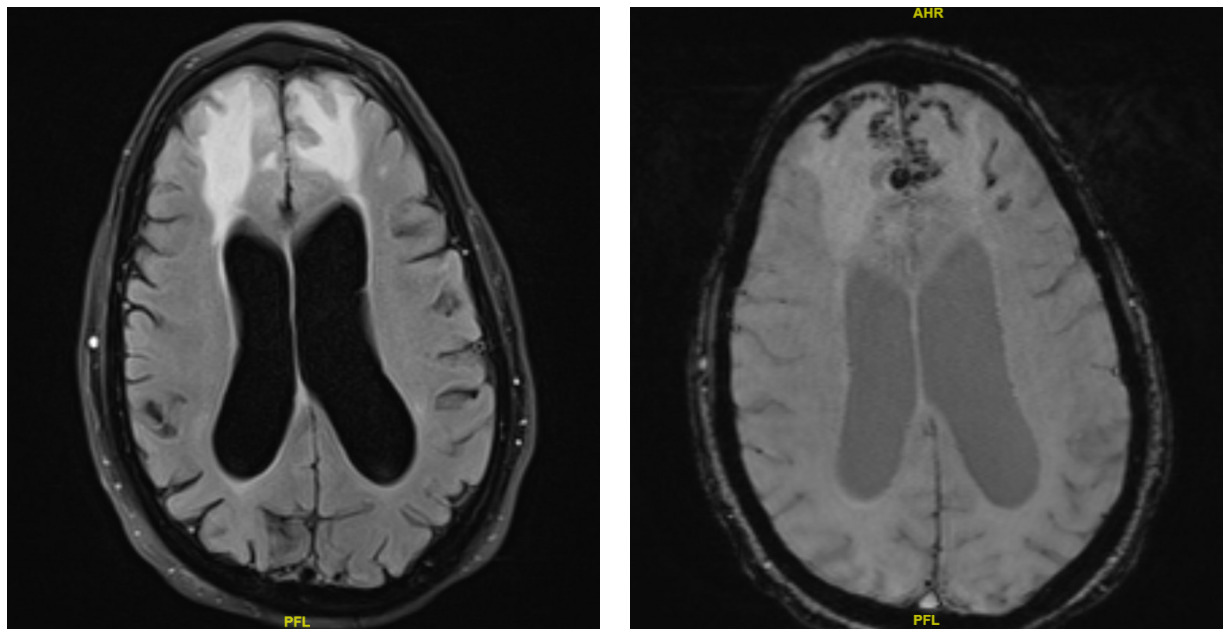

A CT brain was performed in the emergency department, which showed vasogenic edema in the bilateral frontal lobes with trace subarachnoid hemorrhage and hemorrhagic contusion in the right frontal lobe. A repeat CT performed six hours later showed no interval change. The patient was subsequently admitted, and both neurosurgery and neurology were consulted. They recommended initiating IV dexamethasone for vasogenic edema and IV levetiracetam for seizure prophylaxis. A routine EEG showed diffuse theta background slowing, suggesting an underlying mild to moderate diffuse encephalopathy without focal epileptiform discharges. An MRI of the brain was performed, which showed bifrontal vasogenic edema with both superficial siderosis and microhemorrhages, consistent with cerebral amyloid angiopathy-related inflammation (CAA-RI) (Figure 1).

In patients who meet the criteria for probable CAA-RI, empiric immunosuppressive therapy may be initiated to avoid the need for brain biopsy. If there is no clinical or radiographic improvement after approximately three weeks of treatment, a biopsy should then be considered. The presence of patchy or confluent T2 hyperintensities on MRI, along with strictly lobar microbleeds or cortical superficial siderosis on susceptibility-weighted imaging, supports the diagnosis of CAA-RI. MRI findings of T2 white-matter hyperintensities, combined with pathological evidence of vascular Aβ-associated inflammation, further reinforce the diagnosis.4